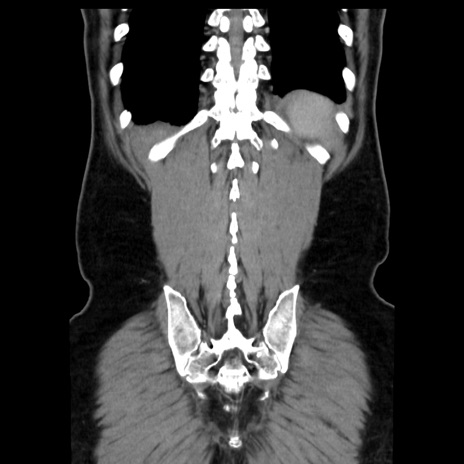

症例16(冠状断像)

【現病歴】 約1ヶ月前より間欠的に腹痛と嘔吐あり、当院消化器内科を受診したところCTで多発する肝臓のLDAを指摘され、精査中であった。以降は消化器症状は安定していたが、2日前より嘔気と腹痛があり、同日より排便・排ガスが消失した。改善認めず、 本日、救急外来を受診した。

【身体所見】意識清明・会話良好、BT 36.3℃、BP 127/80mmHg、 P 80bpm、腹部:膨満あり、平坦・軟、上腹部正中および下腹部正中に圧痛あり、反跳痛なし、筋性防御なし。